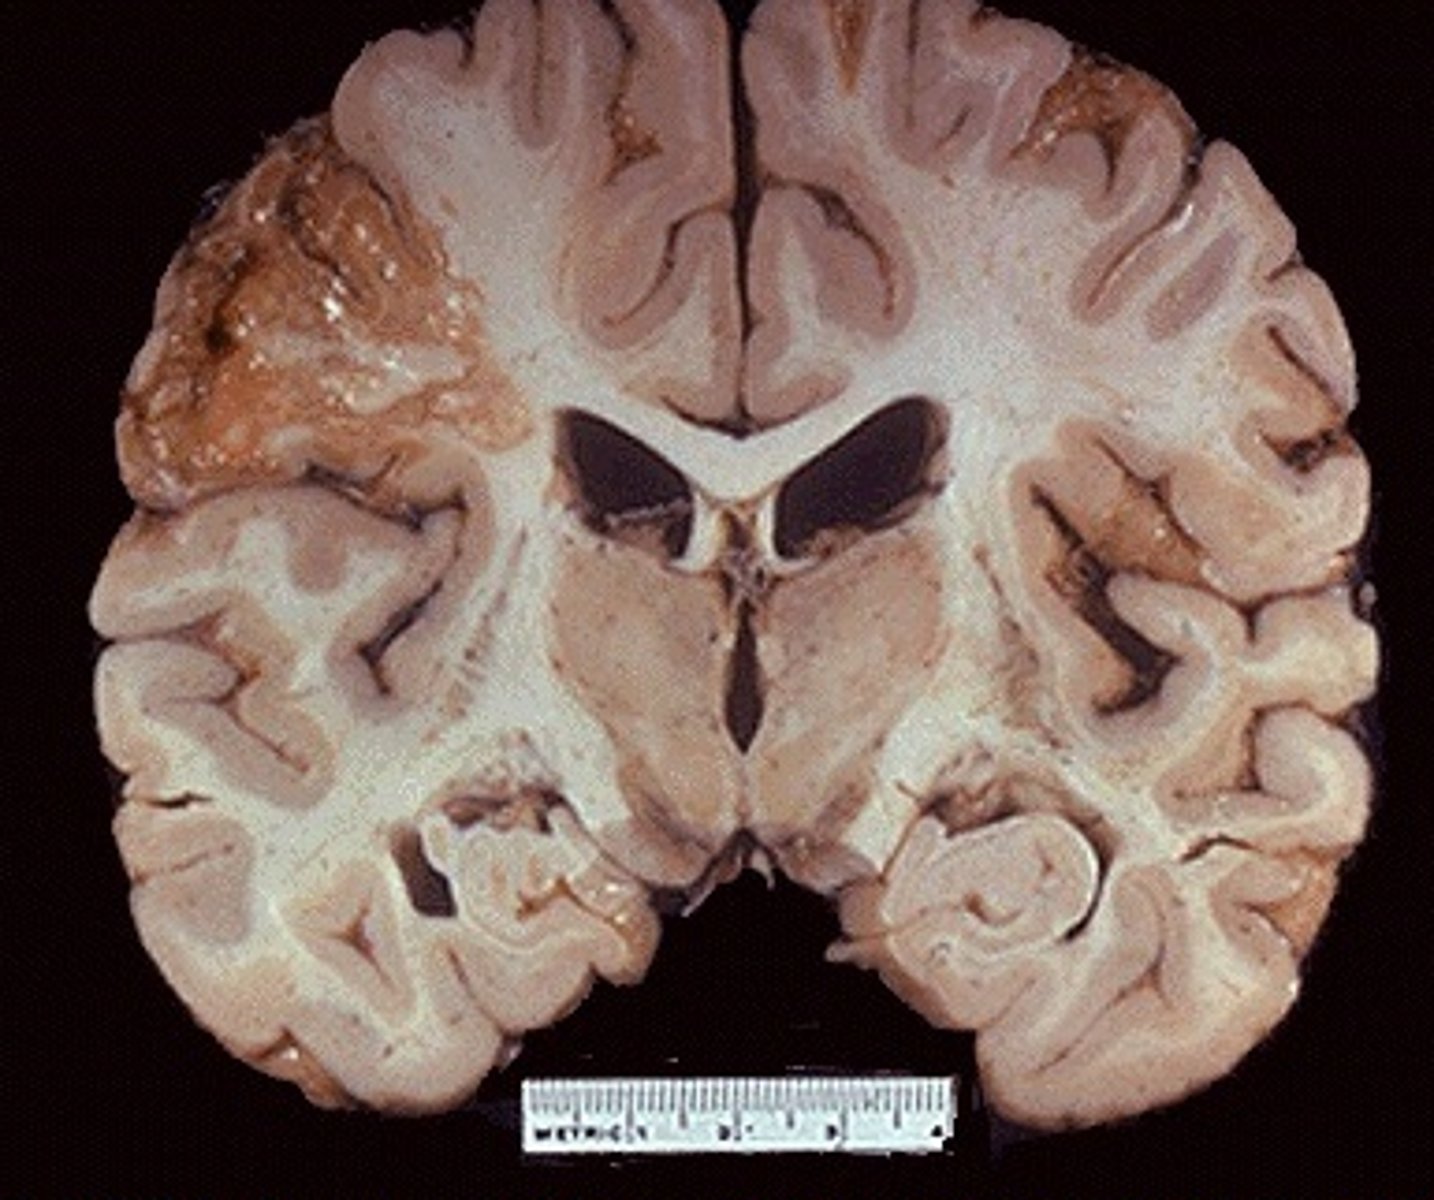

necrotic cell death (liquefactive)

-brain & neurons

-walled-off liquid goo